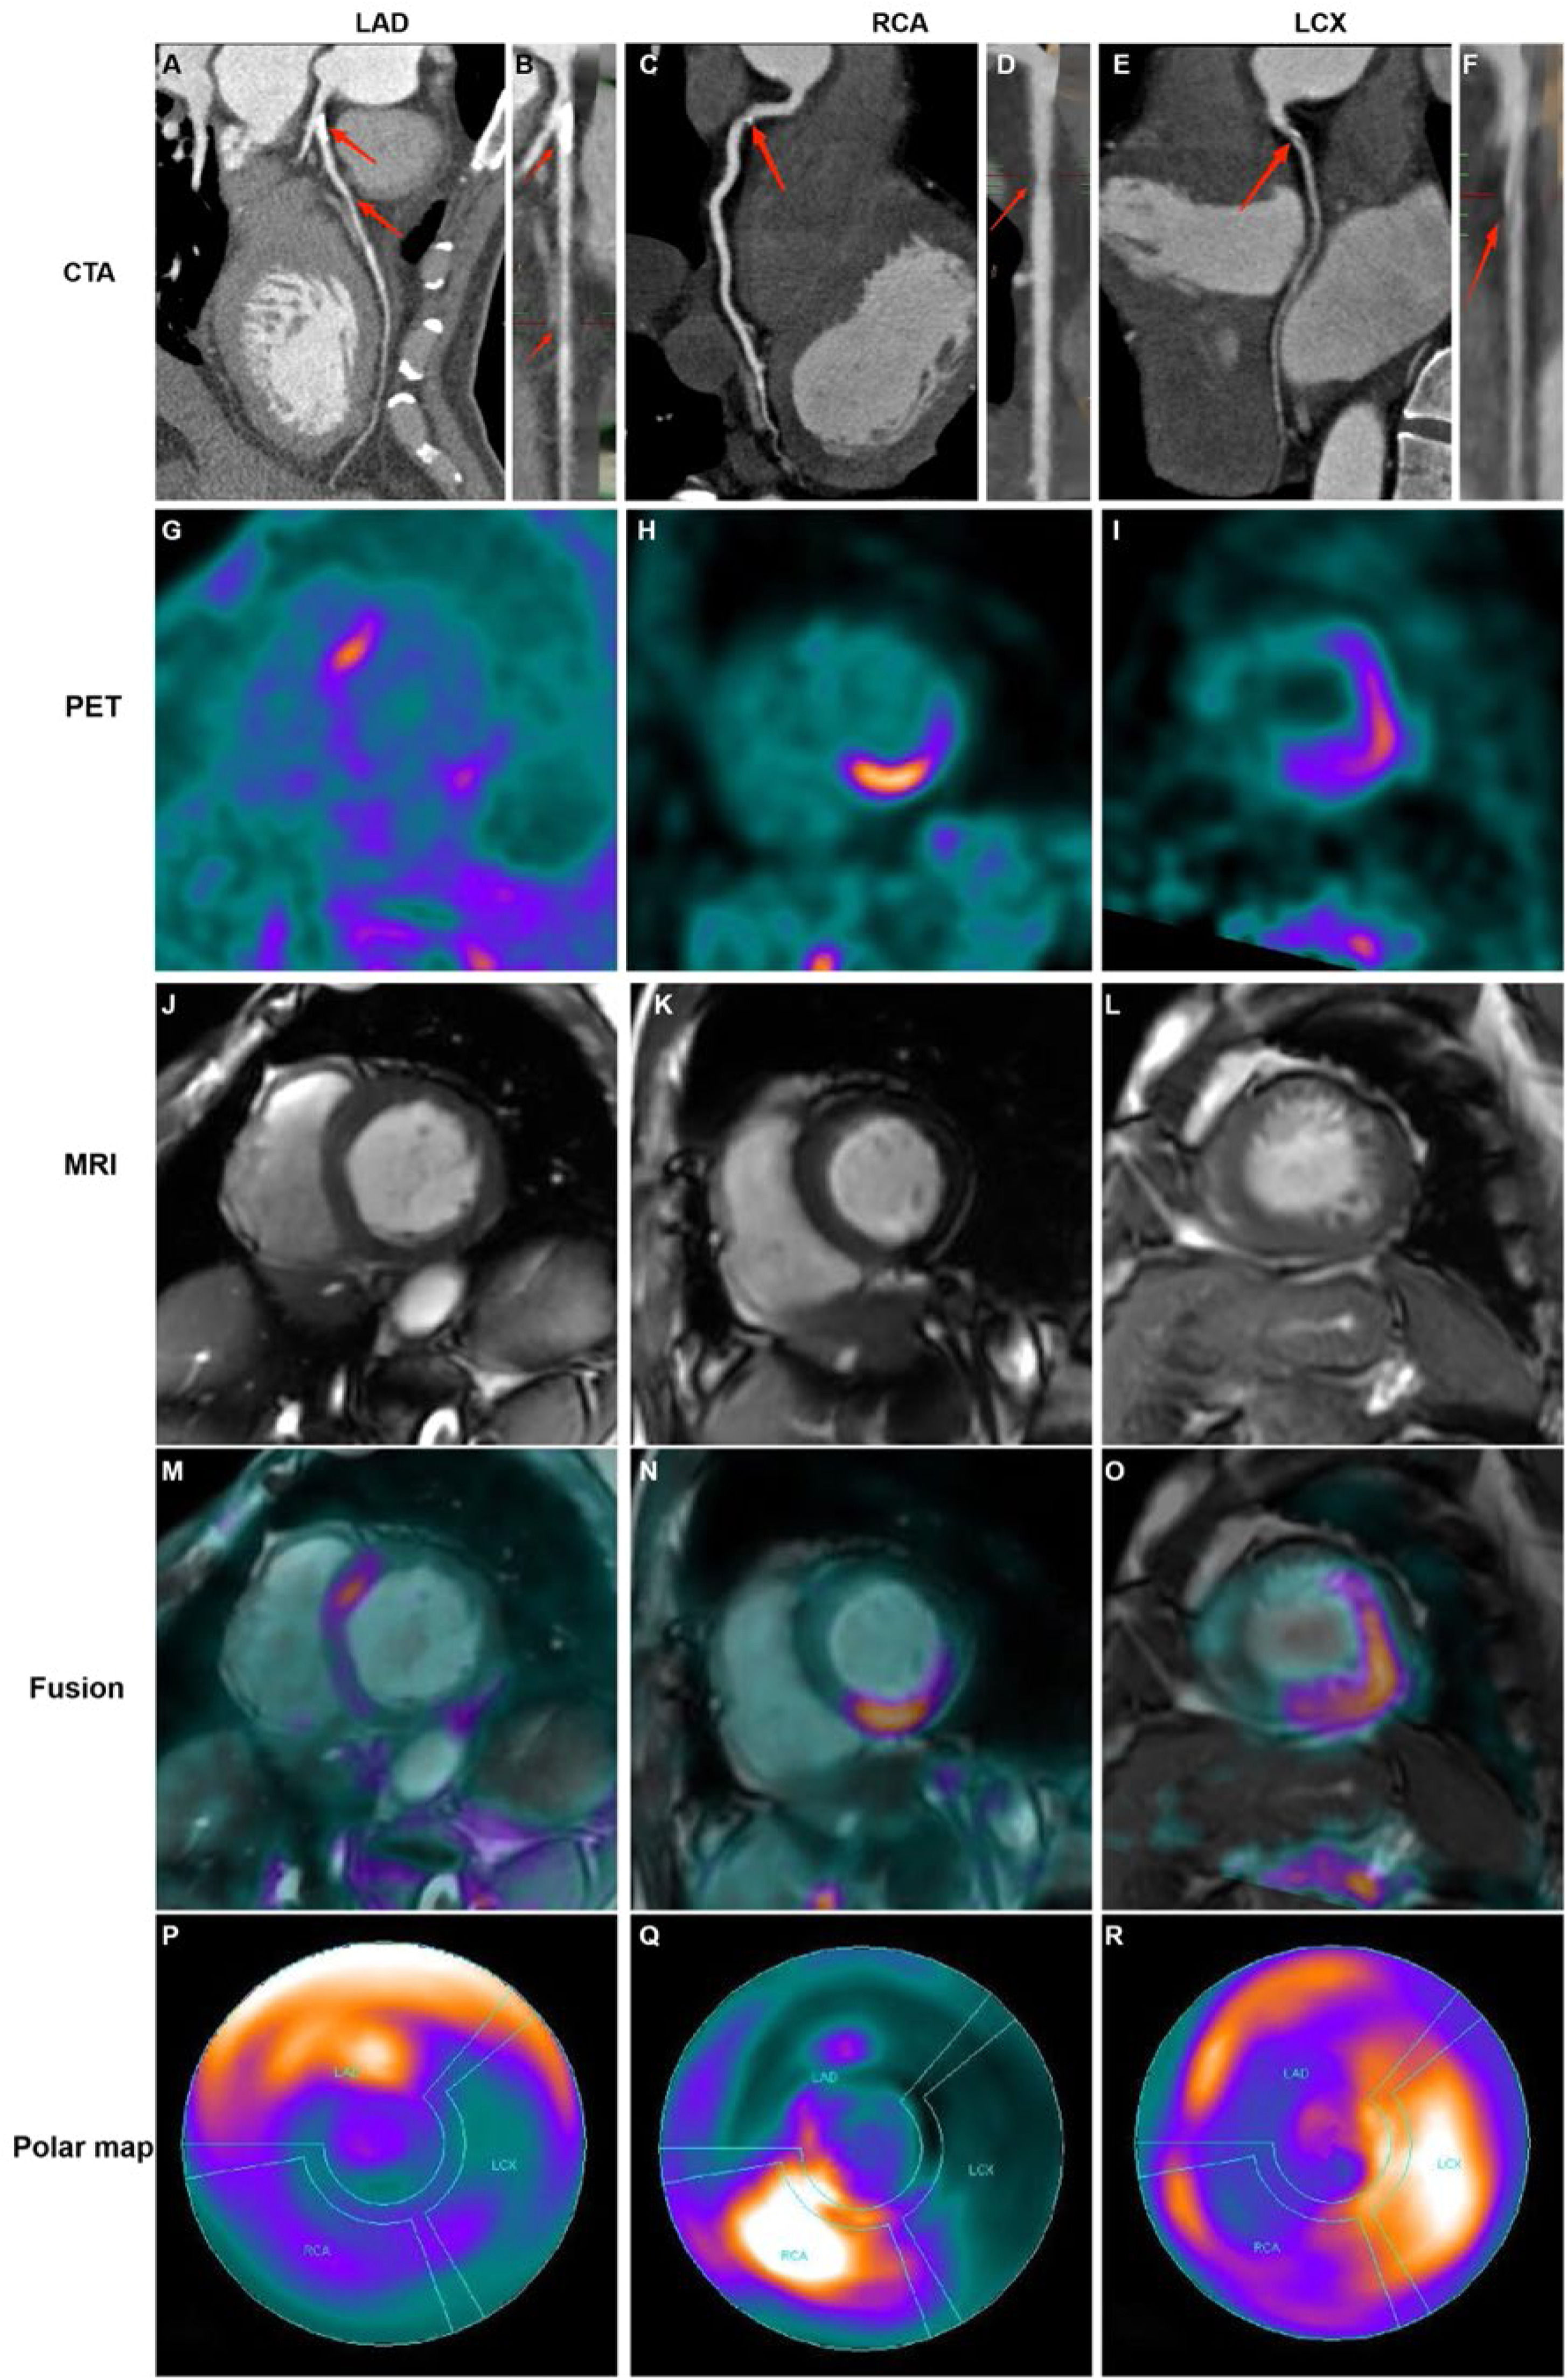

Distributions of FAPI uptake in patients with CADThe LV myocardial wall was divided into three parts based on the blood-supplying areas of the main coronary arteries, LAD, RCA, and LCX areas, which are shown in the polar maps from the short-axis view of the cardiac PET images (Fig. 3). Myocardial regions supplied by coronary arteries diagnosed as stenotic by CTA exhibited abnormally high FAPI uptake. Moreover, FAPI-uptake was significantly higher in areas supplied by the occluded coronary artery than in those with normal blood supply in the same CAD patients (all p-values ˂ 0.05; Fig. 4A and Table 2).

Representative images in participants with coronary stenosis. Curved reconstruction map (A, C, E) and probe map (B, D, F) obtained from Computed Tomography Angiography (CTA) showed the vascular stenosis (indicated by red arrow). 18F-FAPI PET images (G, H, I), MRI images (J, K, L), and PET/MR fusion image (M, N, O) in short-axis cine showed that FAPI was up-taken in a certain slicer. The distribution of FAPI-uptake in the left ventricle was presented with a polar map (P, Q, R). The first column showed images in a 42-year-old man with 50% stenosis in Left Anterior Descending coronary artery (LAD) and 30% stenosis in Right Coronary Artery (RCA). In the short-axis cardiac PET/MR fusion images, the uptake of FAPI in the septum was higher (M), and in the polar map of PET images, the anterior and septal wall had higher uptake (P). The second column showed images in a 61-year-old woman with 40% stenosis in RCA. FAPI-uptake increased in the inferoseptal and inferior wall in the short-axis cardiac PET/MR fusion images and the polar map of PET images (N and Q). The third column showed images in a 67-year-old man with 50% stenosis in Left Circumflex Artery (LCX), 30% stenosis in LAD and 30% stenosis in RCA. The FAPI uptake was significantly increase in the lateral wall, and slightly increase in the anterior, septal and inferior wall in the short-axis cardiac PET/MR fusion images and the polar map of PET images (O and R).